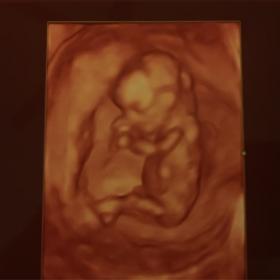

Told Boy at 13 weeks & told Girl at 16 weeks

went to an elective ultrasound at 13/14 weeks and was told boy but the Cord was between the legs and what she said was to be a "penis" seems way too long and it is also divided like a girl part. I have two boys already and their ultrasounds look completely different. After going to the elective ultrasound I saw my doctor at 16 weeksinformed us it was a girl and based off of the earlier ultrasound he gave us it looks girl also. Both my boys at 12 weeks were clear as day and this time my 13 week ultrasound from doctor had nothing between the legs.

I think the elective u/s gave us the wrong determination. Could this be a girl with swollen parts or cord over the girl parts? Attachment 28204Attachment 28205Attachment 28206Attachment 28207Attachment 28208